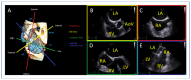

Mitral regurgitation (MR) is a common valvular heart disease associated with significant morbidity and mortality. For patients at high or prohibitive surgical risk, mitral transcatheter edge-to-edge repair (M-TEER) offers a less invasive alternative to surgery. This review outlines key aspects of patient selection and procedural planning for M-TEER, with a focus on clinical and echocardiographic criteria essential for success. Comprehensive imaging-especially 2D and 3D transesophageal echocardiography-is critical to assess leaflet anatomy, coaptation geometry, and mitral valve area. Selection criteria differ between primary and secondary MR and are guided by trials such as COAPT and MITRA-FR. Optimal outcomes rely on careful screening, anatomical suitability, and multidisciplinary evaluation. With growing experience and advancing technology, M-TEER has become a transformative option for treating severe MR in non-surgical candidates.